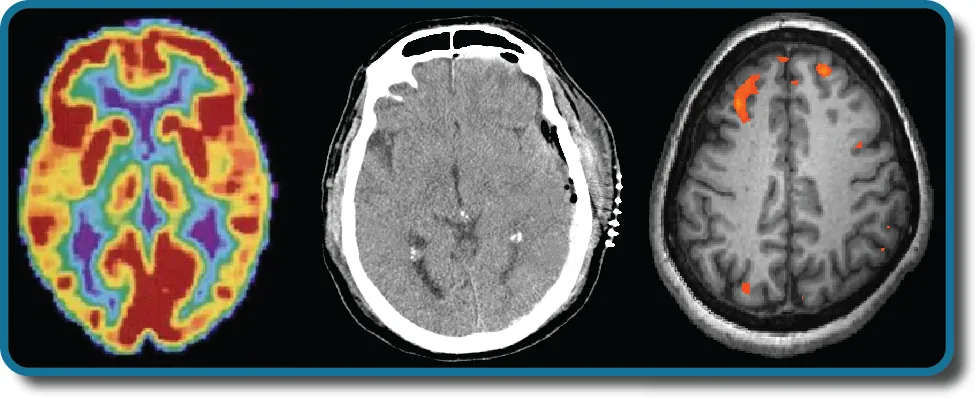

Three brain-imaging scans are shown.

Figure 3.1 Different brain imaging techniques provide scientists with insight into different aspects of how the human brain functions. Left to right, PET scan (positron emission tomography), CT scan (computed tomography), and fMRI (functional magnetic resonance imaging) are three types of scans. (credit “left”: modification of work by Health and Human Services Department, National Institutes of Health; credit “center": modification of work by "Aceofhearts1968"/Wikimedia Commons; credit “right”: modification of work by Kim J, Matthews NL, Park S.)